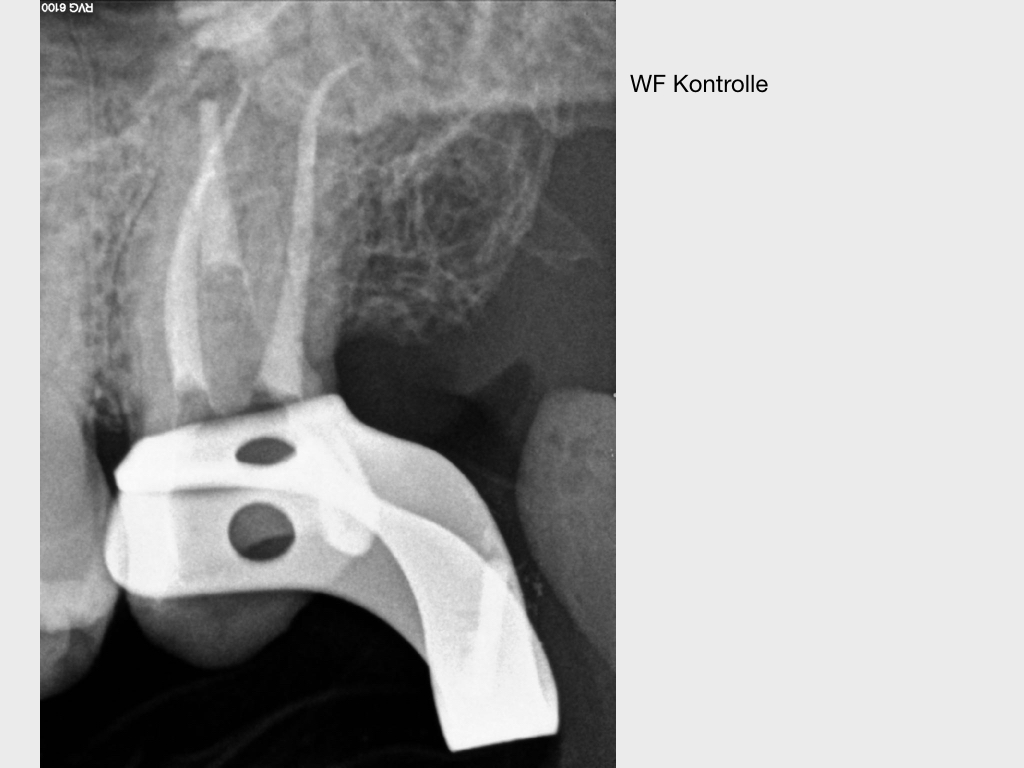

Pick1.014

Pick, Pick (2)